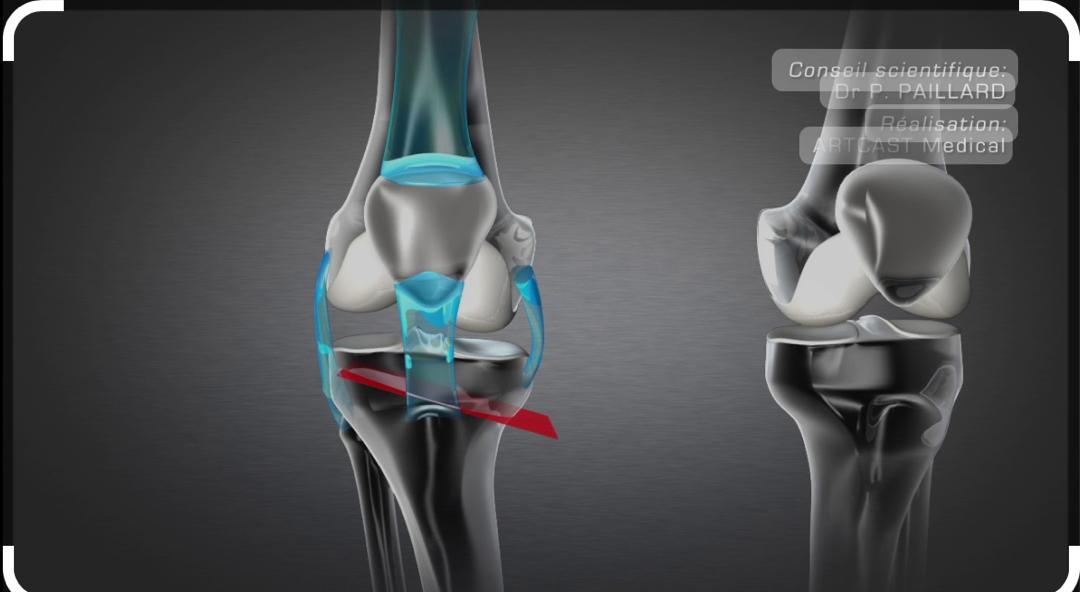

Arthroplastie totale de genou

L'arthroplastie totale de genou est une intervention chirurgicale visant à remplacer l'articulation du genou par une prothèse.